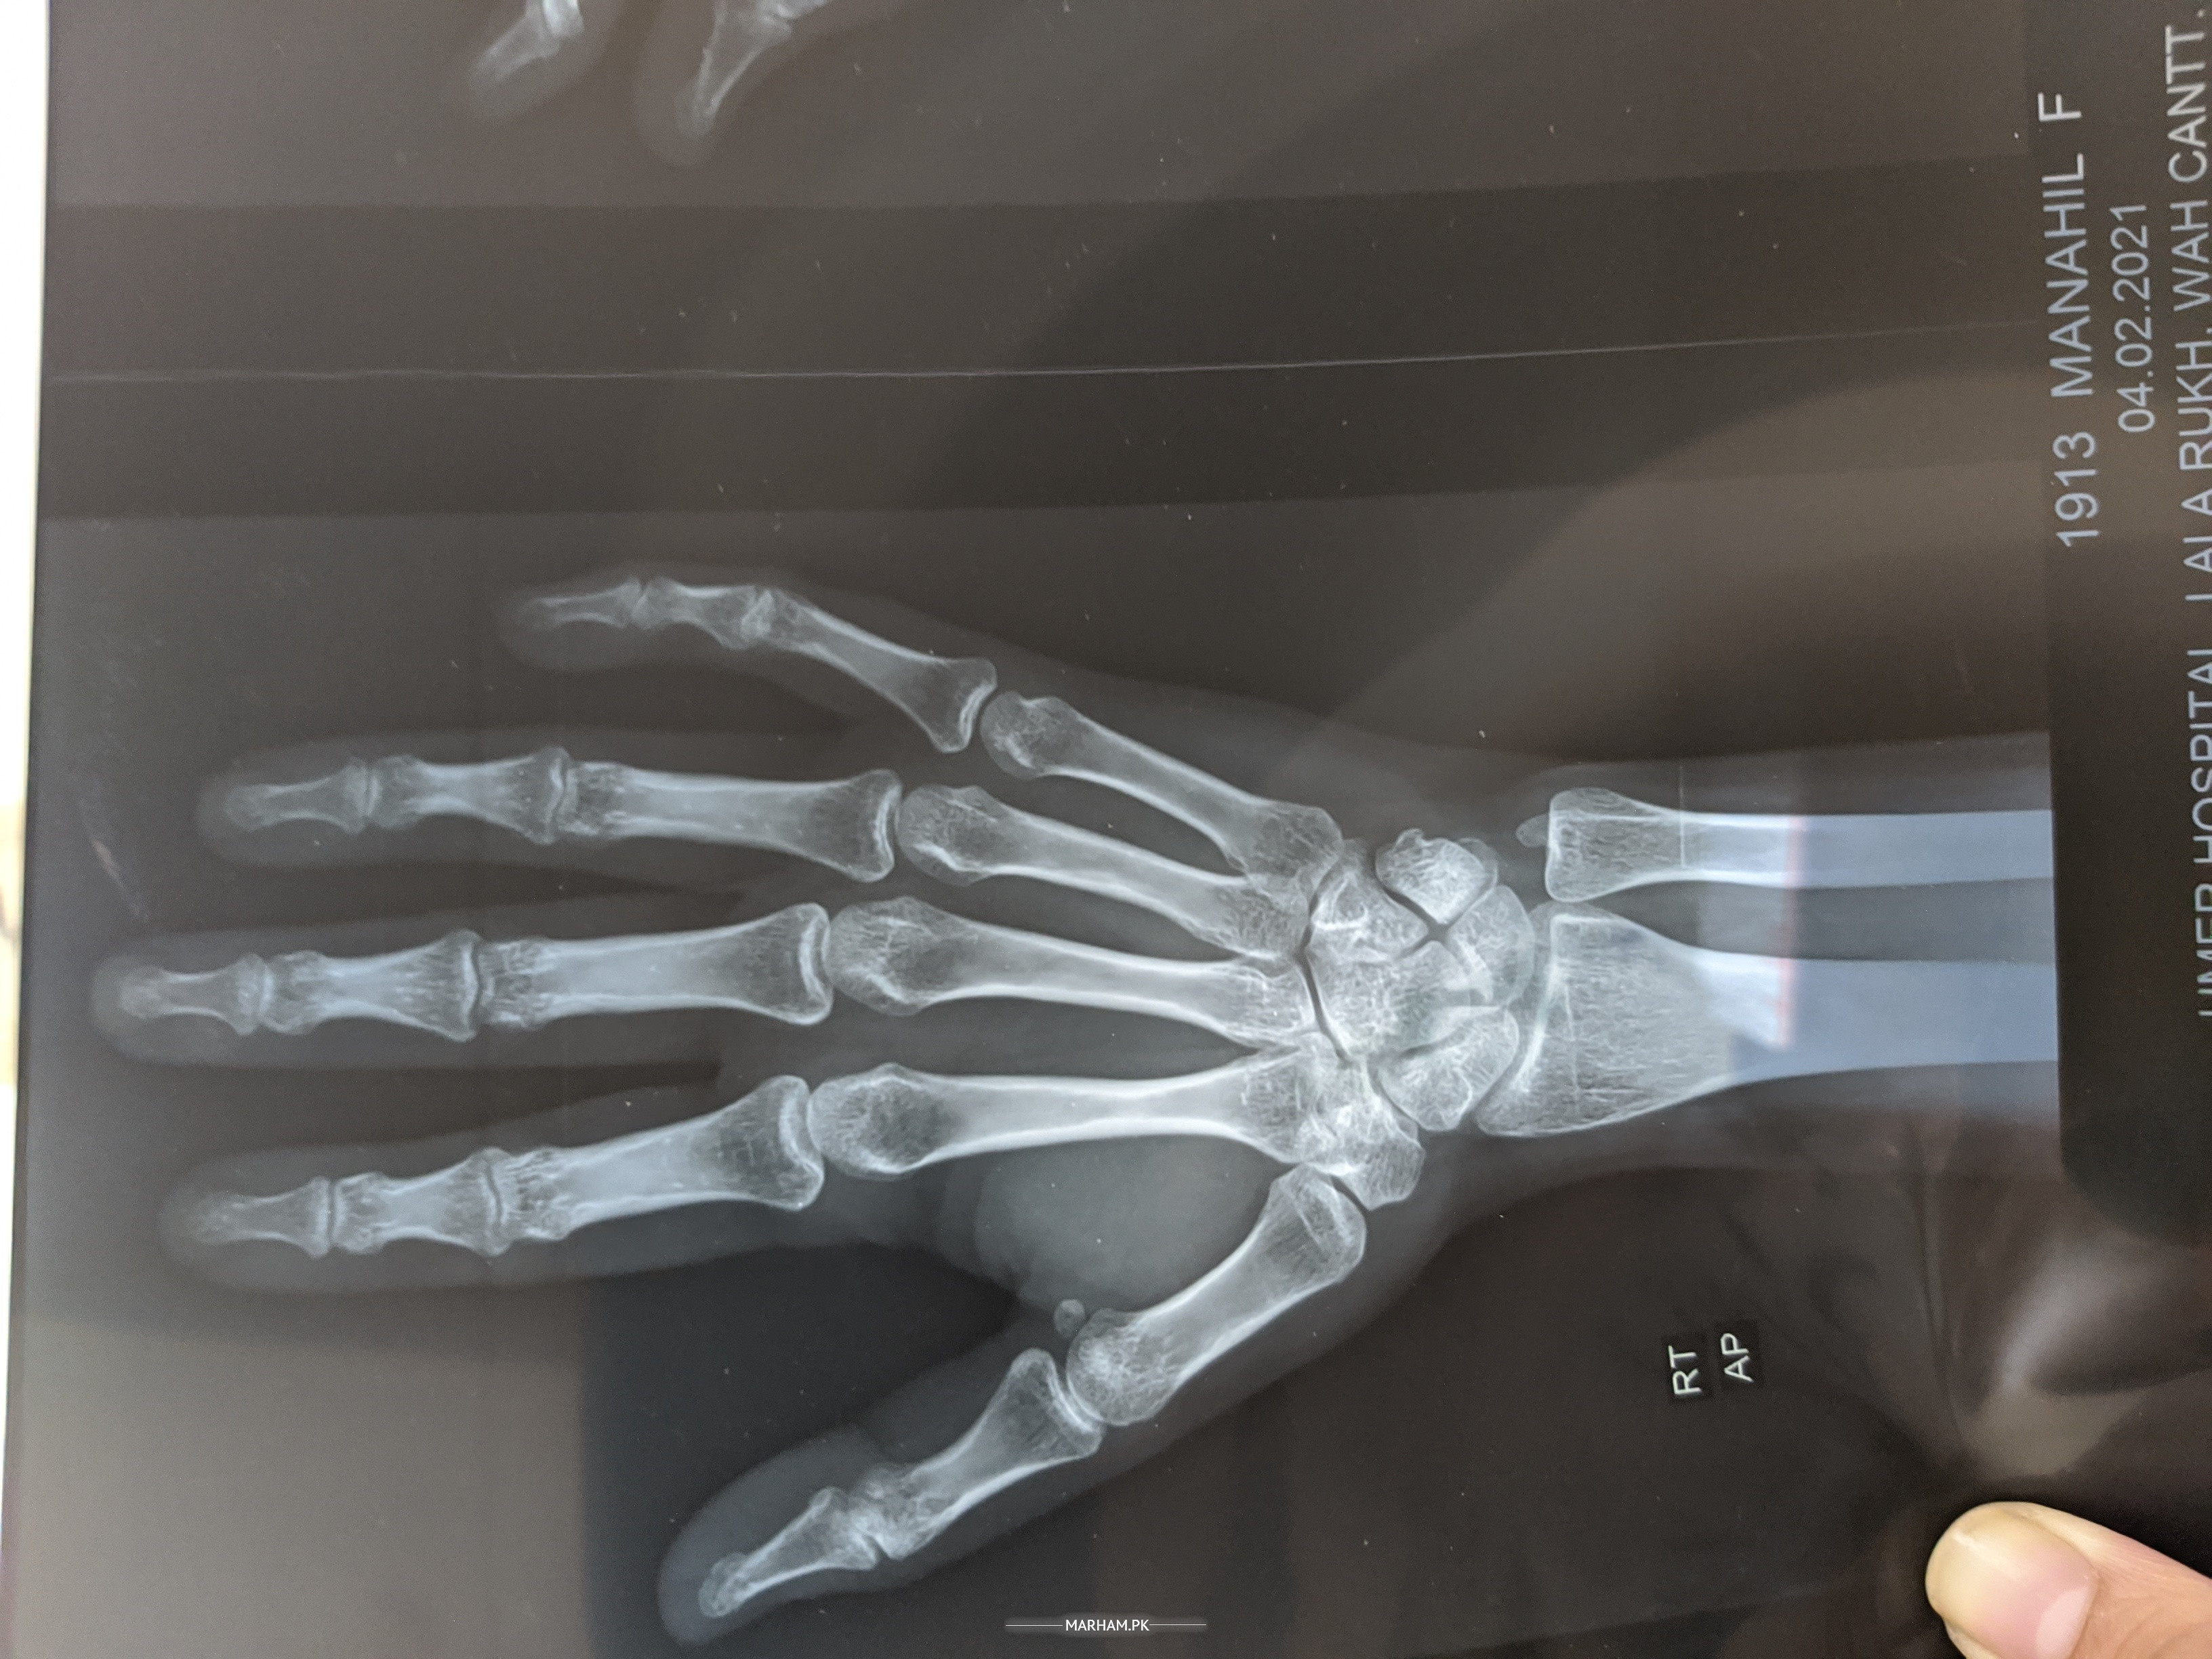

I'm 21 years old but I'm weak. I get unconscious some times..I have severe pain in my right wrist .. I can't bend it and even accidently bended it hurts a lot. I've got my x rays done from various hospitals... each of them said its weakness. please suggest something.

plz share ur x-ray with us do vit D3

Please check I posted my x-rays

X-ray

aap bone density karain aur jo mein nay test deay wo bhi